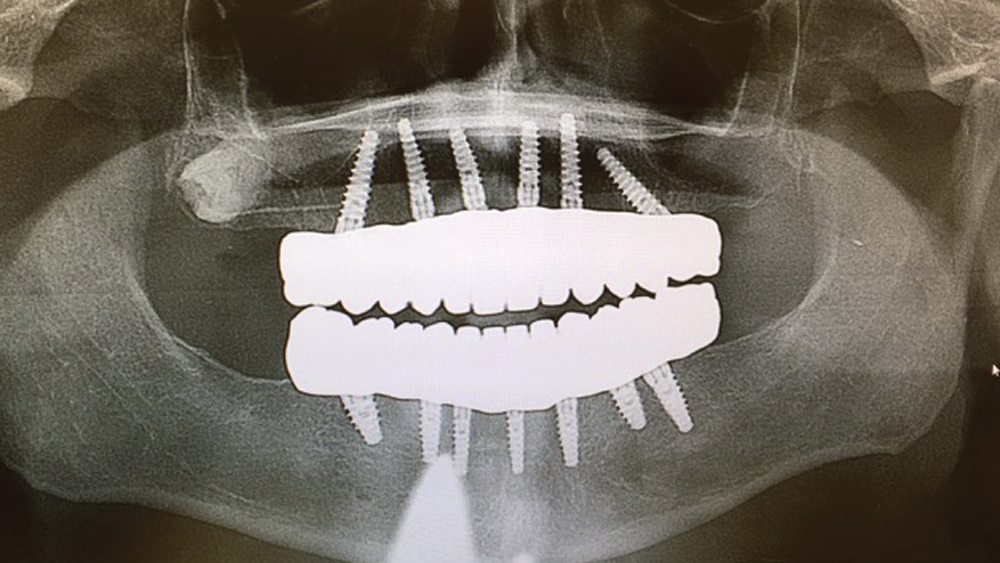

To establish the foundation needed for a screw-retained restoration and avoid fracturing the facial plate, clinicians must position the immediately placed implant against the lingual or palatal wall of the extraction socket. This is one of the reasons I designed the Hahn™ Tapered Implant (Glidewell Direct; Irvine, Calif.) with deep, sharp threads, which enable precise directional control during insertion and prevent the implant from “walking” toward the facial plate as it is threaded into place. This thread design also leads to high primary stability in all bone types, which is essential when performing the extraction with immediate implant placement procedure.1,2

Once osseointegration is complete, the BruxZir® Full-Arch Implant Prosthesis is the ideal choice for the restoration, as its monolithic construction prevents chips, stains, breakage, and dislodged or worn-down prosthetic teeth.3,4 This treatment option has helped elevate the quality of care I’m able to provide for my edentulous patients, who no longer return to my office with a broken acrylic appliance in hand.

The following case demonstrates how to immediately place implants in full-arch indications. By properly positioning the implants, maximizing primary stability and providing the most durable restoration possible, the short- and long-term needs of the patient are addressed in an efficient, predictable manner.